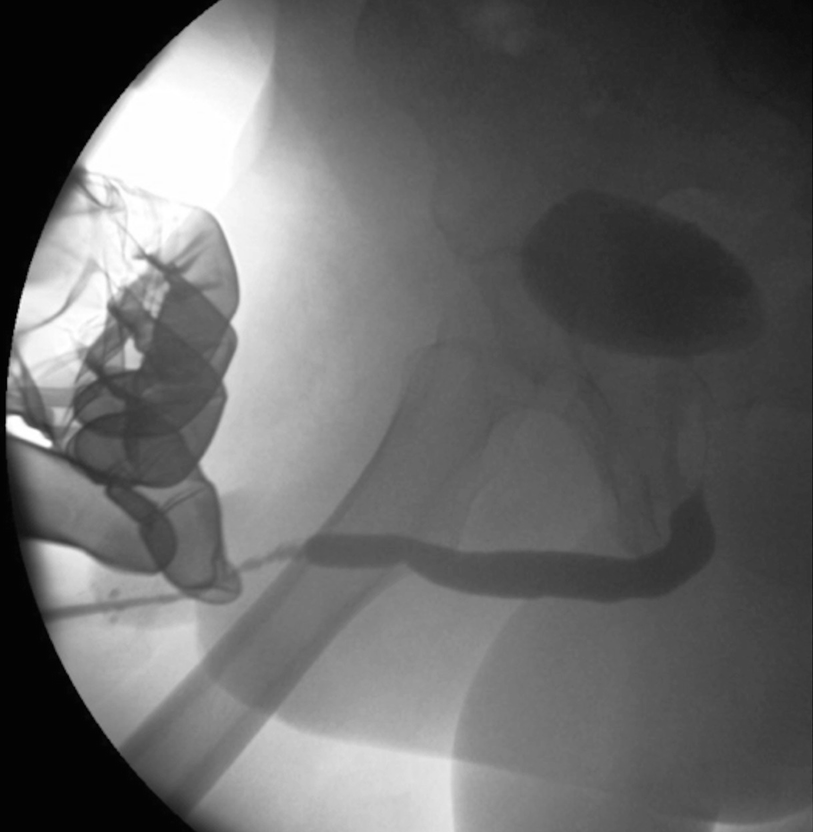

5.3.2 Retrograde Urethrogram and Voiding Cystourethrogram

Proper positioning for retrograde urethrogram. In particular, note the occlusion of the downward left obturator fossa. Also, an incidental urethral stone is also evident

These two urethrograms on the same patient without and with proper oblique positioning demonstrate the importance of proper positioning during urethrogram. Without a sufficient oblique positioning the presence and length of stricture can be underestimated

A short segment bulbar urethral stricture identified on retrograde urethrogram